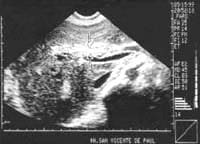

La ecografía hepatobiliar informó una vesícula biliar de 103 x 28 mm, distendida, con paredes engrosadas y con imágenes de múltiples cálculos en su interior.

Se observaron imágenes sugestivas de parásitos inmóviles en la vesícula y el colédoco, el cual estaba dilatado y medía 12 mm (Figuras 1 y 2). La vía biliar intrahepática era hiperecogénica y se encontraba dilatada con imágenes saculares múltiples compatibles con microabcesos.

Figura 1. Ecografía hepática que muestra

un parásitoen el colédoco (flechas).